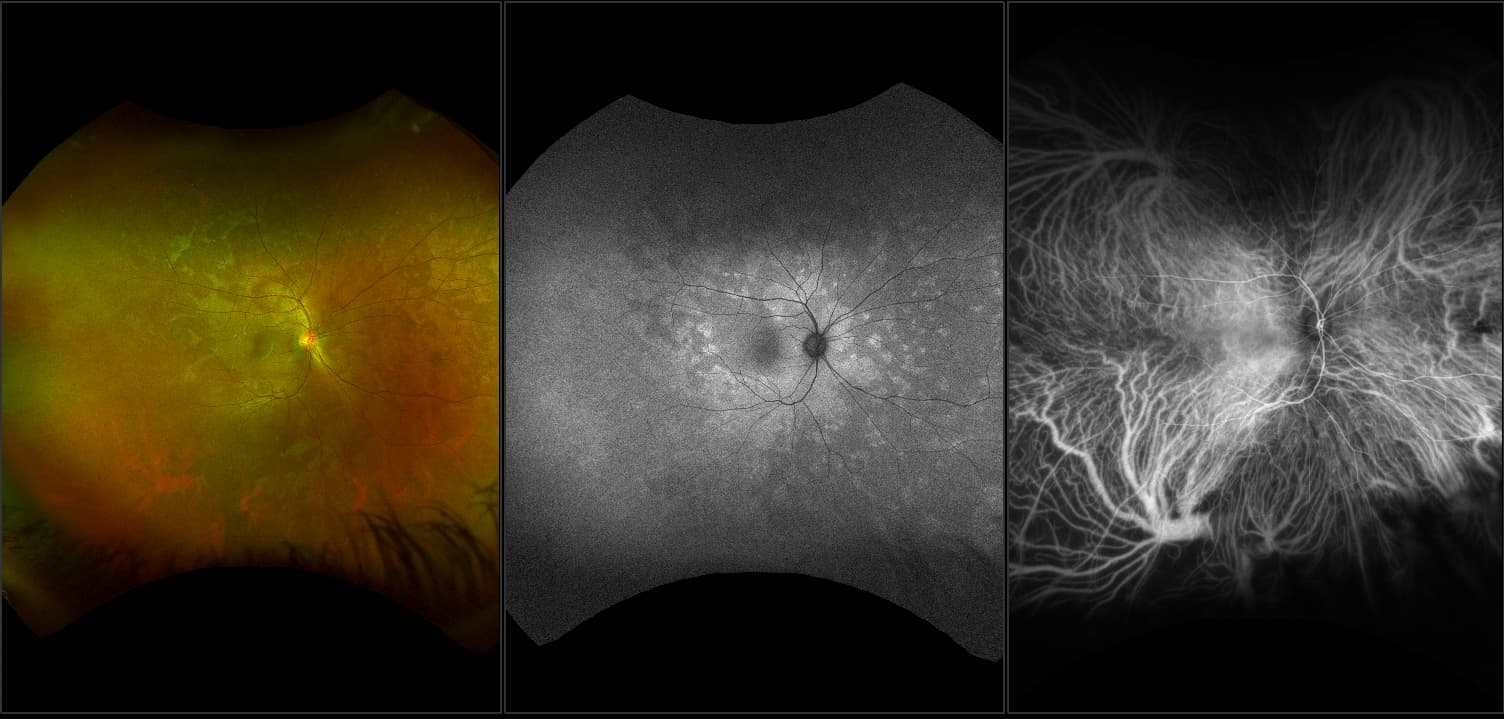

optomap® Recognizing Pathology

This material is designed as a searchable reference resource to support clinical decision-making. The information contained here should be used as general guidance when viewing optomap and OCT images from Optos devices. The differential diagnosis should be made under the direction of the responsible physician. These images were taken on the latest ultra-widefield optomap devices.

optomap Recognizing Pathology is searchable by pathology and/or optomap image modality. You may search by multiples of each selection. Each individual case is represented by the accompanying thumbnail image. Most cases include several different optomap image modalities. To view a full description of the case, please click on the thumbnail. Each image in the case will be made available through our OptosAdvance software which provides multi-dimensional visualization of digital images to aid in the analysis of anatomy and pathology. Support and pathology definitions can be found by selecting one of the buttons, above. Should you have questions, please complete the form below.